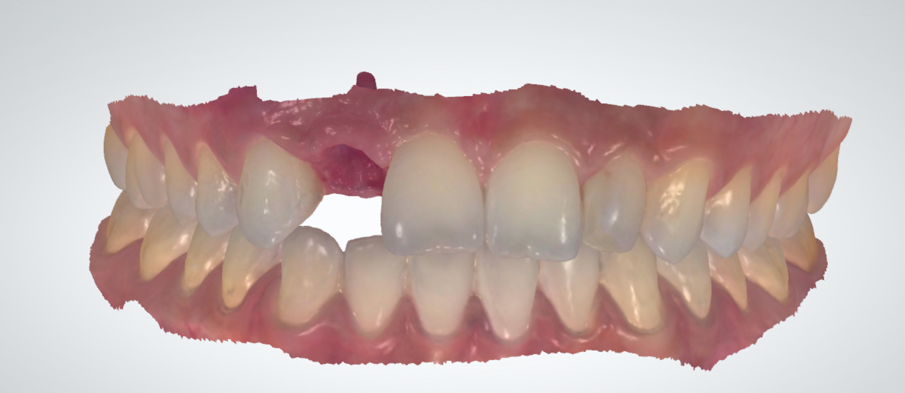

Gli esami radiografici completano l’approccio diagnostico iniziale e lo studio delle radiografie endorali del gruppo frontale, di un’ortopantomografia delle arcate dentarie e di una CBCT permettono di evidenziare un corretto allineamento radicolare degli elementi dentari contigui all’edentulia da trattare e una moderata atrofia orizzontale della cresta alveolare edentula (Fig. 1). Trattandosi di una riabilitazione del settore frontale è opportuno realizzare una dettagliata analisi estetica supportata da un esame fotografico corredato di fotografie extraorali (del volto e del sorriso), fotografie intraorali e da una ceratura diagnostica. L’attenzione iniziale è rivolta principalmente all’analisi dei tessuti molli e degli elementi dentari; in particolare, nel caso descritto, la paziente non presenta fattori estetici sfavorevoli dal momento che si riscontra la presenza di una linea del sorriso media, elementi dentari in area estetica sani e non discromici, fenotipo gengivale spesso, simmetria della festonatura gengivale e buona rappresentazione delle papille interdentali. Osservando in visione frontale la situazione clinica iniziale si evidenzia una lieve recidiva ortodontica dell’elemento 1.1 che si presenta leggermente mesializzato e vestibolarizzato rispetto alla sua posizione ideale (Fig. 2).

Fig. 2 - Situazione clinica iniziale (visione frontale).